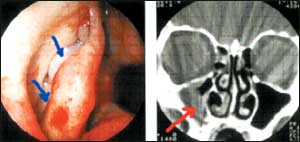

لحميات الأنف والجيوب الأنفية من أكثر الأمراض شيوعاً

اللحمية الأنفية والجيوب الأنفية

*ماهو تعريف اللحمية الأنفية وماهي مسبباتها وهل للوراثة علاقة بها؟

- اللحميات الأنفية هي عبارة عن تمدد للغشاء المخاطي للأنف محدثا نتوء مثل الكيس الصغير يتعلق في ممرات الأنف وذلك بسبب زيادة في إنتاج السائل داخل الخلايا.........